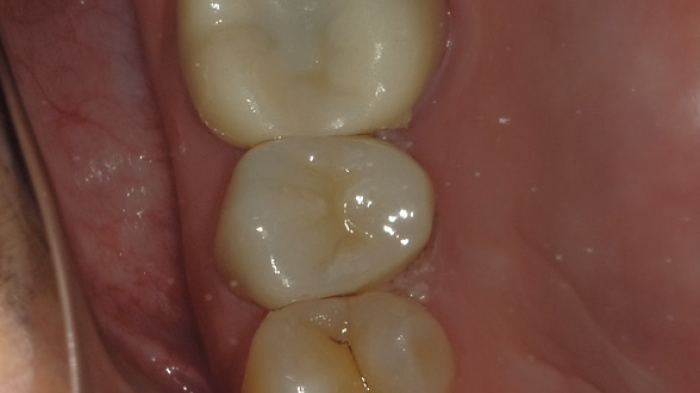

On peut considérer que la couronne est réalisée avec précision si aucune contraction ou expansion du matériau n'est observée.

Cela peut être réalisé à condition que la formation de l'ancrage, la préparation de l'empreinte et la mesure de l'occlusion soient toutes effectuées de manière précise. Dans le cas présenté, la couronne n'a nécessité aucun ajustement avant d'être fixée sur la dent.